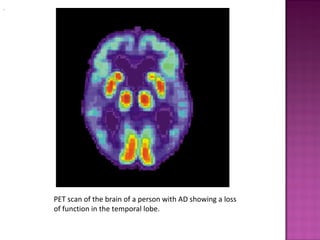

   Advanced medical imaging with computed

tomography (CT) or magnetic resonance imaging

(MRI), and with single photon emission computer

tomography (SPECT) or positron emission tomography

(PET) can be used to help exclude other cerebral

pathology or subtypes of dementia.

PET scan of the brain of a person with AD showing a loss

of function in the temporal lobe.

   When available as a diagnostic tool, SPECT and PET

neuroimaging are used to confirm a diagnosis of

Alzheimer's in conjunction with evaluations involving

mental status examination. In a person already having

dementia, SPECT appears to be superior in differentiating

Alzheimer's disease from other possible causes, compared

with the usual attempts employing mental testing and

medical history analysis.